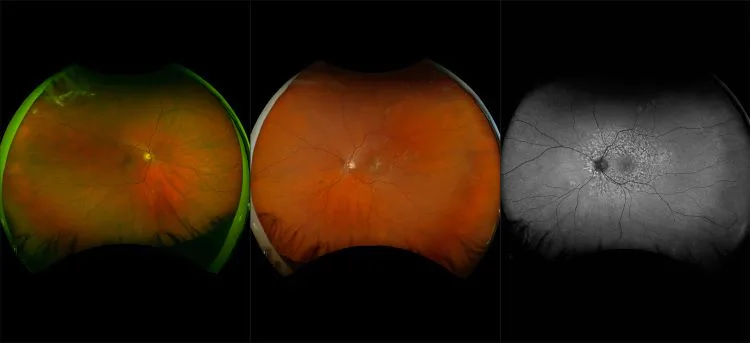

MonacoPro - Dry AMD with IOL and ERM, RG, OCT

Age-related macular degeneration is found in two forms 1. Dry early form. 2. Wet (serous leakage or whole blood). Early dry form typically has drusen (usually around 63u) and RPE degeneration and only needs periodic follow-ups, intermediate dry form has large drusen (>125u) and RPE degeneration and proliferation which requires examinations every 3 to 6 months depending on the severity of the presentation.